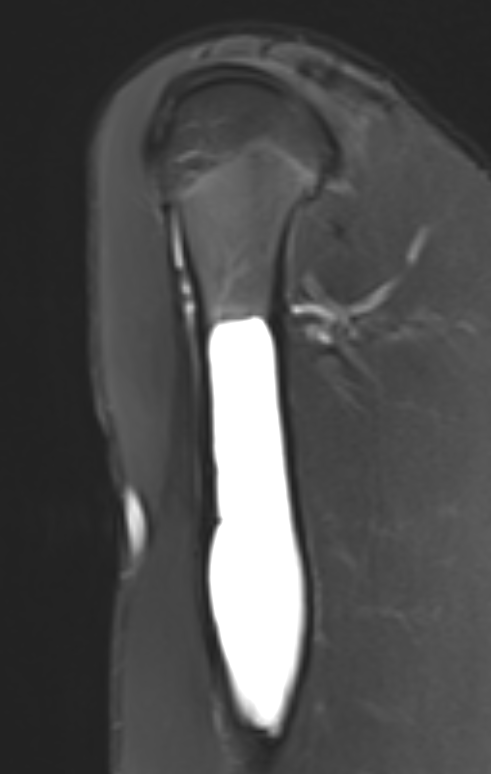

MRI

Gruenewald et al Br J Radiol 2023

- 36 patients with UBC or ABC

- fluid fluid levels / septation seen in both

- arterial feeders on MRA helped differentiate some ABC's